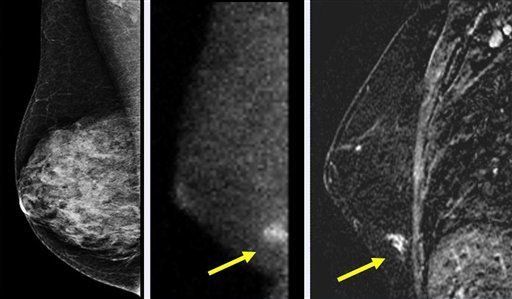

WASHINGTON (AP). El objetivo es tener una mejor forma de buscar indicios de cáncer en mujeres con senos demasiado densos para que los mamogramas actuales puedan proporcionar una imagen clara.

El que los radiólogos empleen lentes de tercera dimensión no es la única ayuda potencial. La Clínica Mayo en Rochester, Minnesota, está probando una nueva cámara para examen de seno que podría desafiar las imágenes de los mucho más costosos exámenes de resonancia magnética que actualmente se aplican a las mujeres con mayores riesgos de desarrollar la enfermedad, a una fracción de su precio.

Los mamogramas son exámenes de rayos X que buscan manchas densas en tejido de seno normal, sombras que podrían detectar tumores. Realizarse mamogramas con regularidad a partir de los 40 años de edad ayuda a reducir las muertes por cáncer de seno al encontrar tumores cuando son más pequeños y más tratables.

Sin embargo, están lejos de ser perfectos, y los senos densos podrían ser el mayor obstáculo para los rayos X.